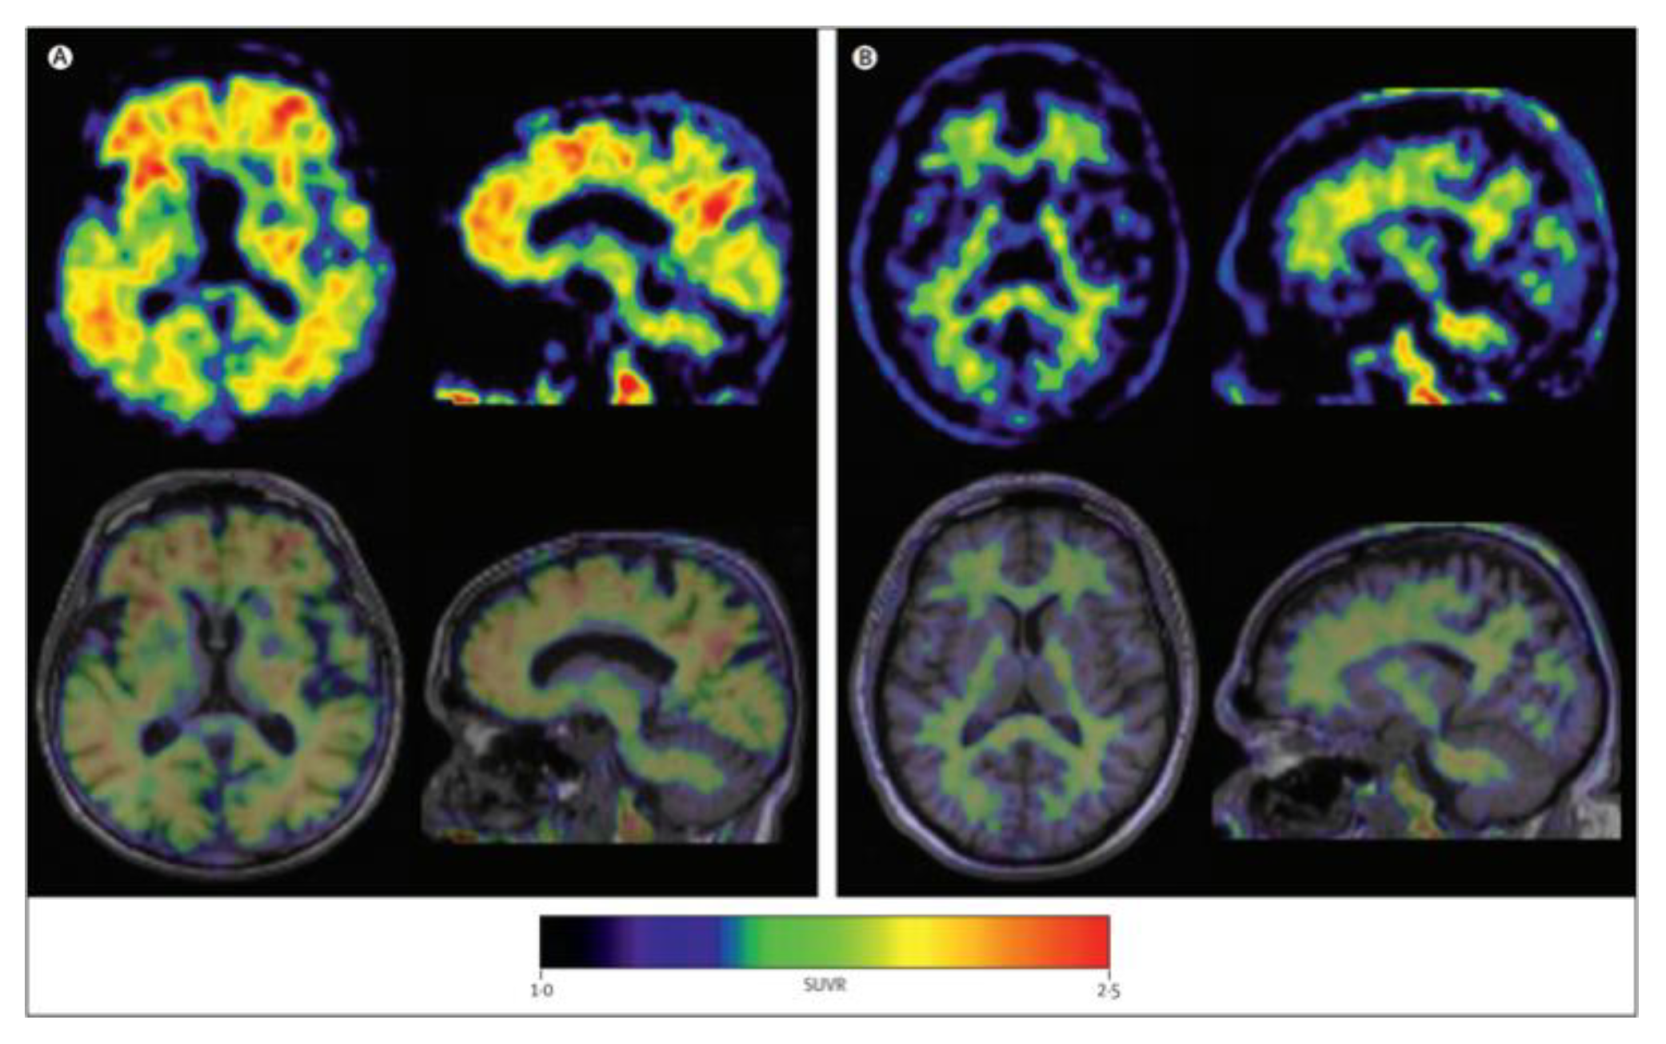

Figure 4.

Axial and sagittal (18F)florbetaben brain PET images of an AD patient (A) and a healthy control (B) for the detection of Aβ [56]. The bottom row illustrates a fused PET/T1-weighted MRI image. Pet images were acquired 90–110 min post-injection. Images are reprinted with permission of the publisher [56].

Lastly, (18F)flutemetamol was FDA approved in 2013 and is an 18F derivative of PIB, thus demonstrating similar kinetic properties [54]. PET scans were able to distinguish healthy controls to AD patients with a sensitivity of 97.2% and specificity of 85.3% (Figure 5) [57].